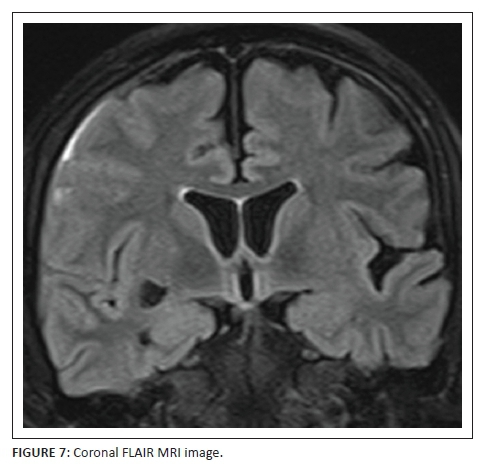

MRI study of the brain was arranged to further elucidate the cause of this unusual presentation. T2-weighted (Figure 5) and T1-weighted (Figure 6) MRI sequences confirmed the right frontal gyral swelling with effaced right middle and superior frontal sulci. Subtle gyral swelling was also observed in the parasagittal left frontal precentral region. Figure 7, a coronal FLAIR image showed, in addition to the frontal gyral swelling, an extra-axial fluid collection over the right frontal lobe convexity and in the sulci due to a sliver of subdural and subarachnoid blood respectively. A right sublenticular cyst was also incidentally noted.